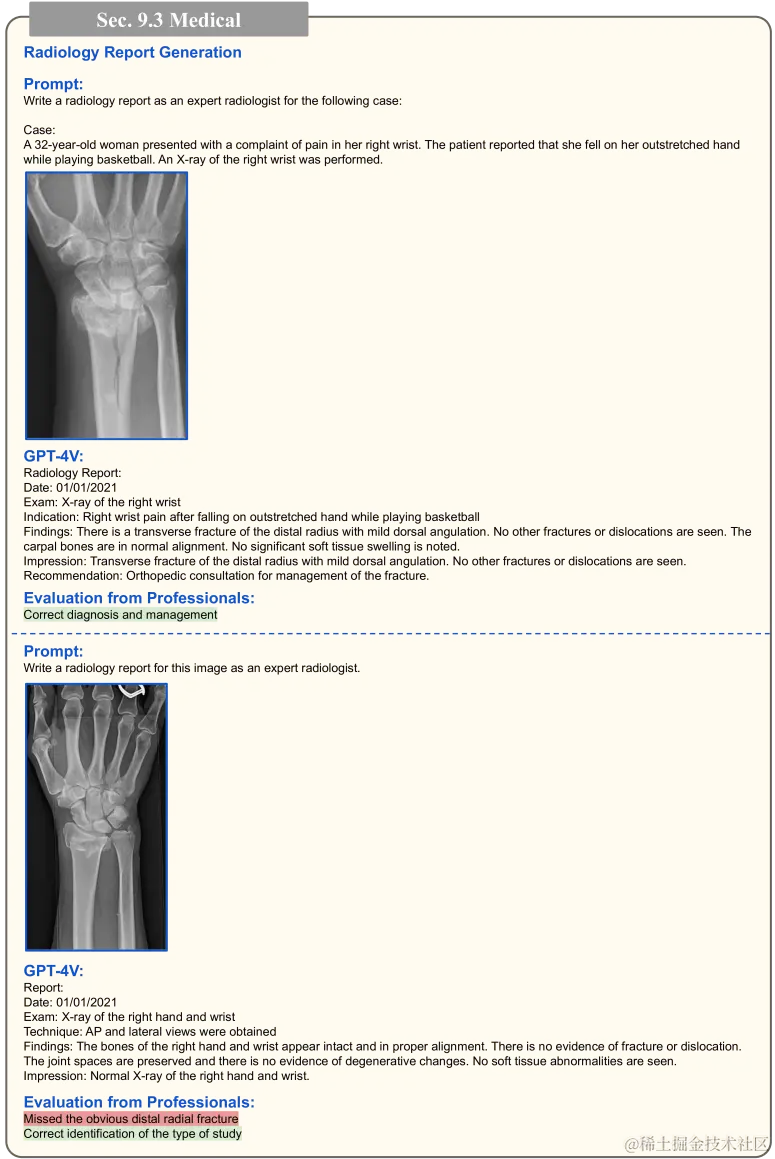

在第 4.1 节,图 18 至图 19 展示了 GPT-4V 在理解医学图像方面的有效性。我们还深入探索了 GPT-4V 在生成放射科报告的应用,如图 75 至图 78 所示。在此,我们提供了多张医学图像,让 GPT-4V 生成完整的放射科报告。由于准确评估报告需要专业知识,我们也征求了医学专家的意见进行评估。

图 75 展示了两个实例:一张是腹部 X 光图,另一张是右膝的 MRI。在这两个案例中,GPT-4V 都准确识别出了检查类型并作出了正确的诊断。接下来,在图 76 中,我们看到 GPT-4V 为手/腕部 X 光图片生成的放射科报告。虽然 GPT-4V 根据第一张 X 光图片成功作出了推荐的治疗方案,但它却遗漏了第二张 X 光图中明显的桡骨远端骨折。然而,生成的报告格式严谨,可以作为模板,帮助医生减轻书写报告的负担。

放射科报告自动生成的重点展示。这些生成的报告会由医疗专家审核,以确定其是否准确无误。

图 75:放射科报告自动生成的重点展示。报告的生成内容经过医疗专家的审核确认无误。其中,绿色高亮的部分已经得到医疗专家的验证,证实报告内容准确无误。有关详细讨论,请参见第 9.3 节。此处的医学图像来源于互联网。

图 76:放射科报告自动生成的重点展示。报告的生成内容经过医疗专家的审核确认无误。其中,绿色和红色的高亮部分分别表示报告内容经过专家验证的准确和不准确之处。详细讨论,请查看第 9.3 节。图中医学图像来自网络。